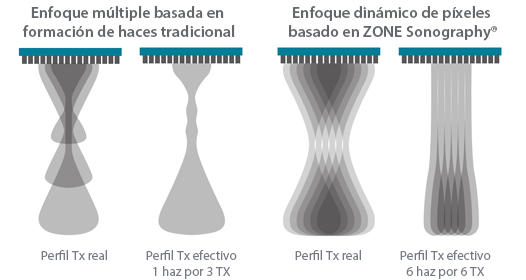

Desde que se fundó la compa?ía, Mindray ha explorado incansablemente nuevas formas de mejorar la confiabilidad del diagnóstico. Con la revolucionaria tecnología de ZONE Sonography?, la nueva plataforma ZST+ de Resona?7 lleva la calidad de la imagen por ecografía a un nivel superior mediante el procesamiento de datos de canal y la adquisición de zona.